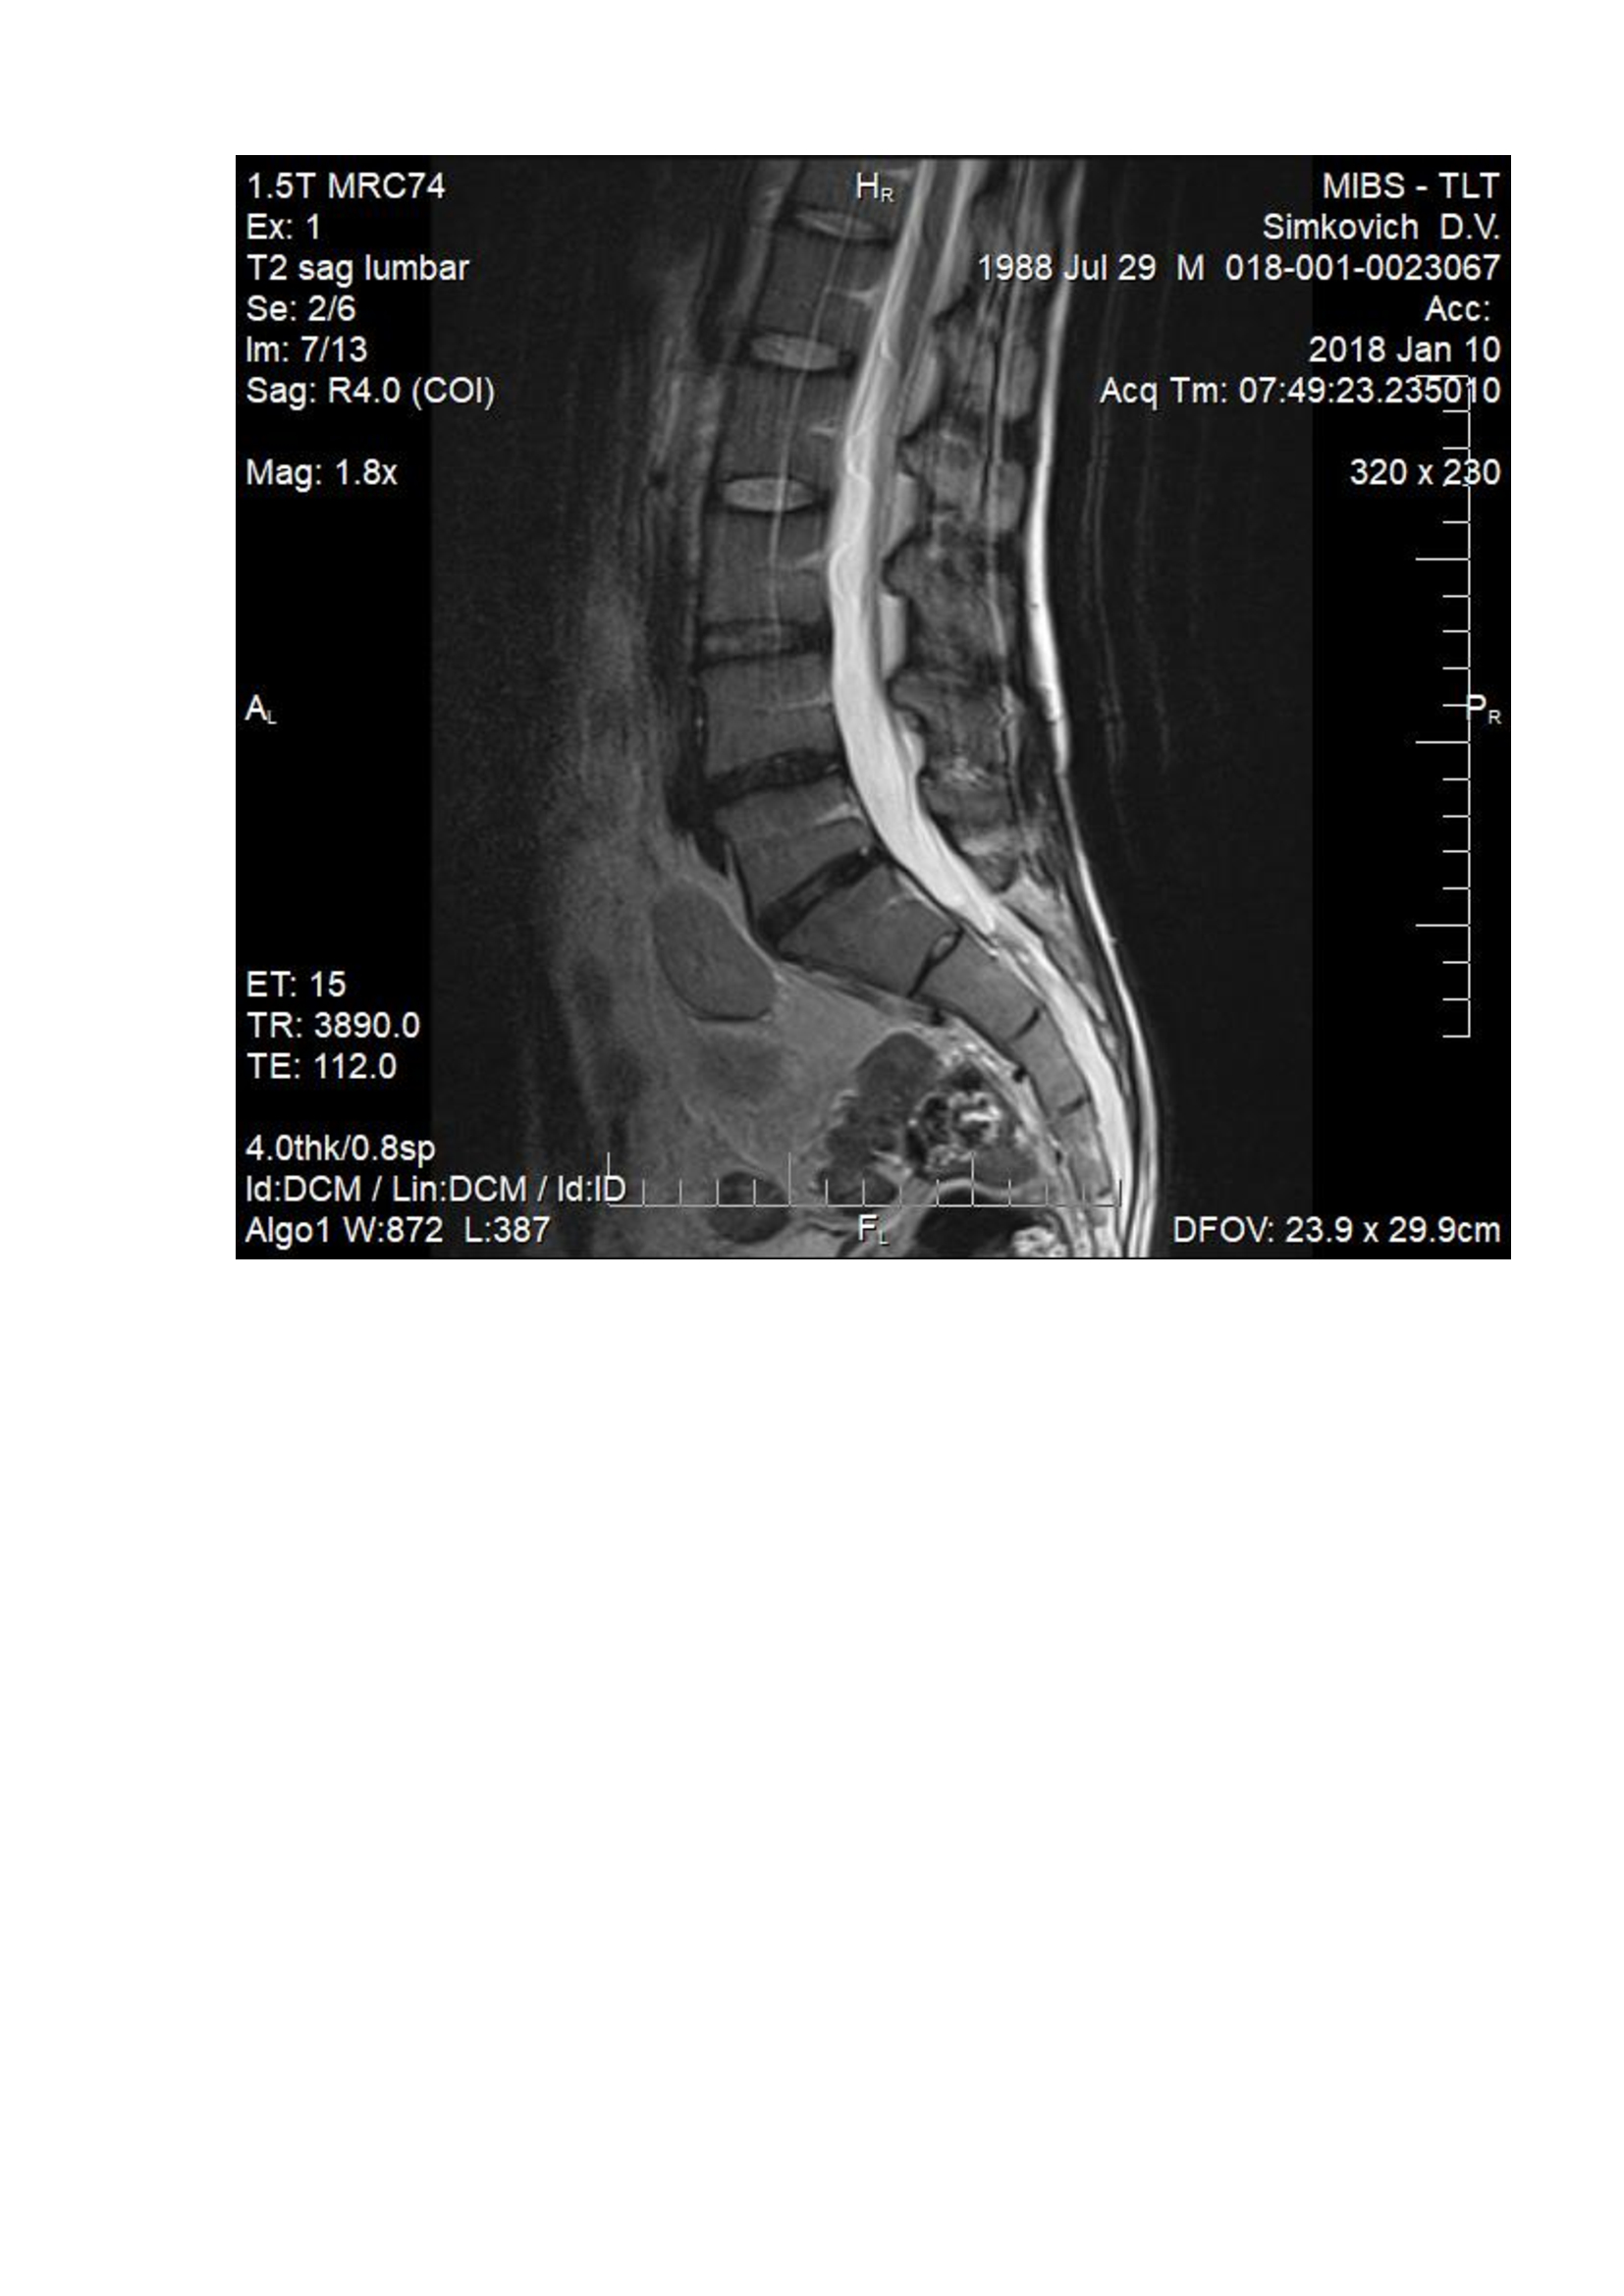

На данный момент болит правая нога, начала побаливать и левая, болит спина. При лежании на спине на ровной поверхности боль в спине проходит. Сделал МРТ. Неврологи нашего города ставят разные диагнозы, от фасеточного синдрома до нестабильности позвоночника. Консервативное лечение не помогает.

Посмотрите пожалуйста мои снимки.

Здравствуйте! судя по снимкам -грыжа удалена. Для определения формирования рубцово-спаечного процесса - мы делаем мрт с в/в контрастом, для определения нестабильности - обычный рентген с функциональными пробами, для определения степени поражения нерва ЭНМГ нижних конечностей. Далее становится понятно в какую сторону двигаться.